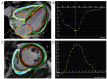

Pulmonary hypertension (PH) is a life-threatening cardiopulmonary disease associated with a poor prognosis, with progressive right ventricular (RV) failure being the main cause of death in this vulnerable population. Right heart catheterization remains the gold standard for assessing pulmonary hemodynamics. However, due to its invasive nature, non-invasive imaging methods are gaining increasing interest. Two-dimensional transthoracic echocardiography serves as the primary screening tool for PH and is widely used to estimate its likelihood. Nevertheless, this technique has several limitations, partially addressed through the assistance of a three-dimensional echocardiography. Cardiac magnetic resonance imaging (CMR) provides a comprehensive evaluation of both the morphology and hemodynamics of right ventricle-pulmonary artery unit, offering essential information for diagnosis, prognosis, and therapeutic monitoring. While two-dimensional cardiac CMR enables non-invasive characterization of pulmonary hemodynamics, advances in 4D-flow cardiac CMR allow for a more detailed analysis. These advancements enable the assessment of flow patterns, energetics, wall shear stress and severity, offering a more nuanced understanding of the disease. This review aims to provide an in-depth summary of the current data on advanced non-invasive imaging techniques for PH.